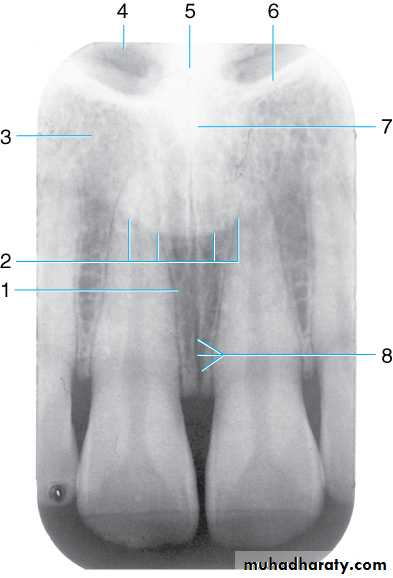

Drawing of maxillary midline area. Shown are the (1) outline of nose, (2) incisive foramen , (3) lateral fossa, (4) nasal fossa, (5) nasal septum, (6) border of nasal fossa, (7) anterior nasal spine, and (8) median palatine suture

Radiograph of maxillary midline area. This radiograph shows the (1) incisive foramen, indicated by an irregularly shaped, rounded radiolucent area. Also seen are the (2) outline of the nose, (3) lateral fossa, (4) nasal fossa (radiolucent), (5) nasal septum (radiopaque), (6) border of nasal fossa, (7) anterior nasal spine, and (8) median palatine suture